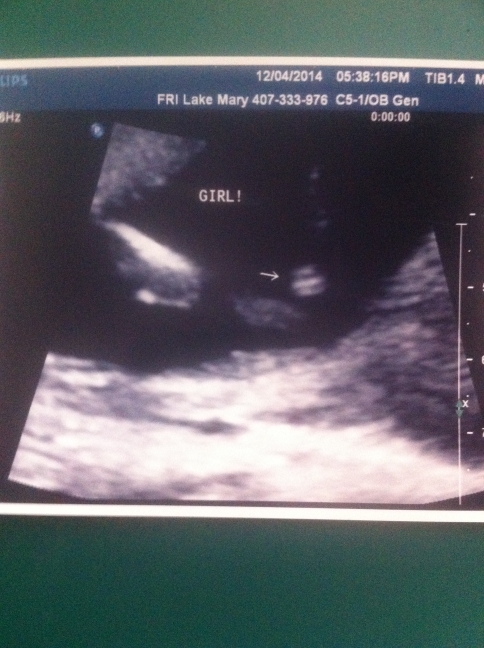

Expert guesses much appreciated!!! measuring 17 weeks

Can i please get some more predictions besides u/s techs. She predicted girl and i just want to be sure :) We had good views but for some reason was unable to get a distinction of what parts were down there and took a while to get these shots. I believe her mentality was no penis = girl as well as three lines. We finally fought for the three line pic and got it, however i feel the angle on those three lines seem weird. Almost perpendicular to the legs instead of parallel along with the legs. I dont know if i am being paranoid or not, I just want to bond with this baby not having this weird feeling of uncertainty that maybe she isn't a girl. Either or, I would just like to be sure of my lil blessing. Thank You everybody

(suppose to be 18w1, measuring 17w0)Attachment 22504Attachment 22503